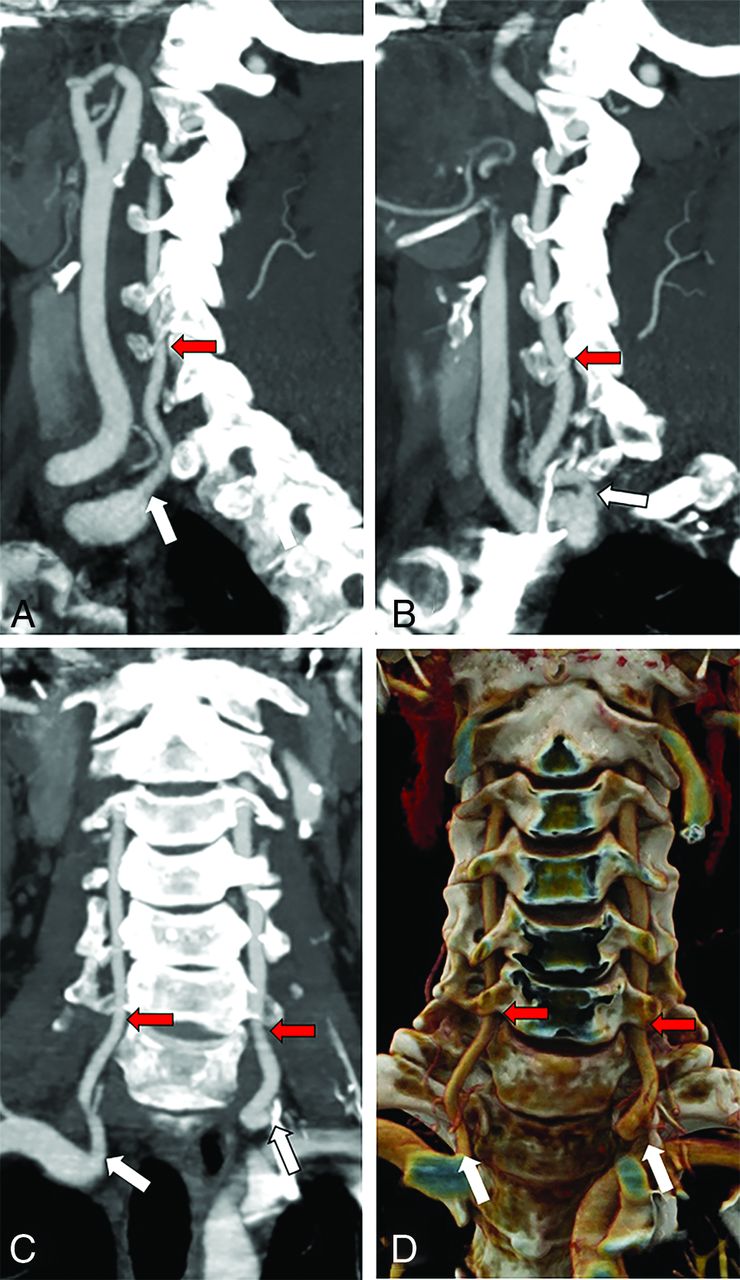

Normal anatomy of the cervical VAs. Sagittal MIPs of the right (A) and left (B) VAs and both in the coronal plane (C), as well as a coronal 3D rendering (D) show the origin of both VAs from the SCAs (white arrows) and their entry into the FT at C6 (red arrows).

CTAs of the neck were obtained for a variety of indications, including stroke, trauma, nontraumatic hemorrhage, vertigo, abnormal findings on carotid Doppler ultrasound, and follow-up for findings noted on earlier studies. CTA was performed according to institutional procedures, by using either a 64- or 128-section scanner (LightSpeed VCT or Revolution GSI, respectively; GE Healthcare) with bolus tracking following administration of Omnipaque 350 (GE Healthcare) into the venous system at a rate of 4 mL/s. Slices (0.625-mm-thick) were obtained from below the aortic arch through the circle of Willis or through the entire head, depending on the indication. Coronal and sagittal reformats were obtained, and MIPs were generated. 3D volume-rendered reformats were generated using dedicated software (Syngo Via; Siemens) (Fig 1). The same software was used to generate the images in subsequent images. Measurements of distances along the parent arteries to the origins of the VAs were obtained by generating curved planar reformats and measuring linear distances along the parent vessels (Fig 2). Cases with VA variants were identified and compiled in a deidentified file on a Health Insurance Portability and Accountability Act–compliant encrypted server. This study was exempted from institutional review board review by the Rutgers University Institutional Review Board (Pro 2022000874).